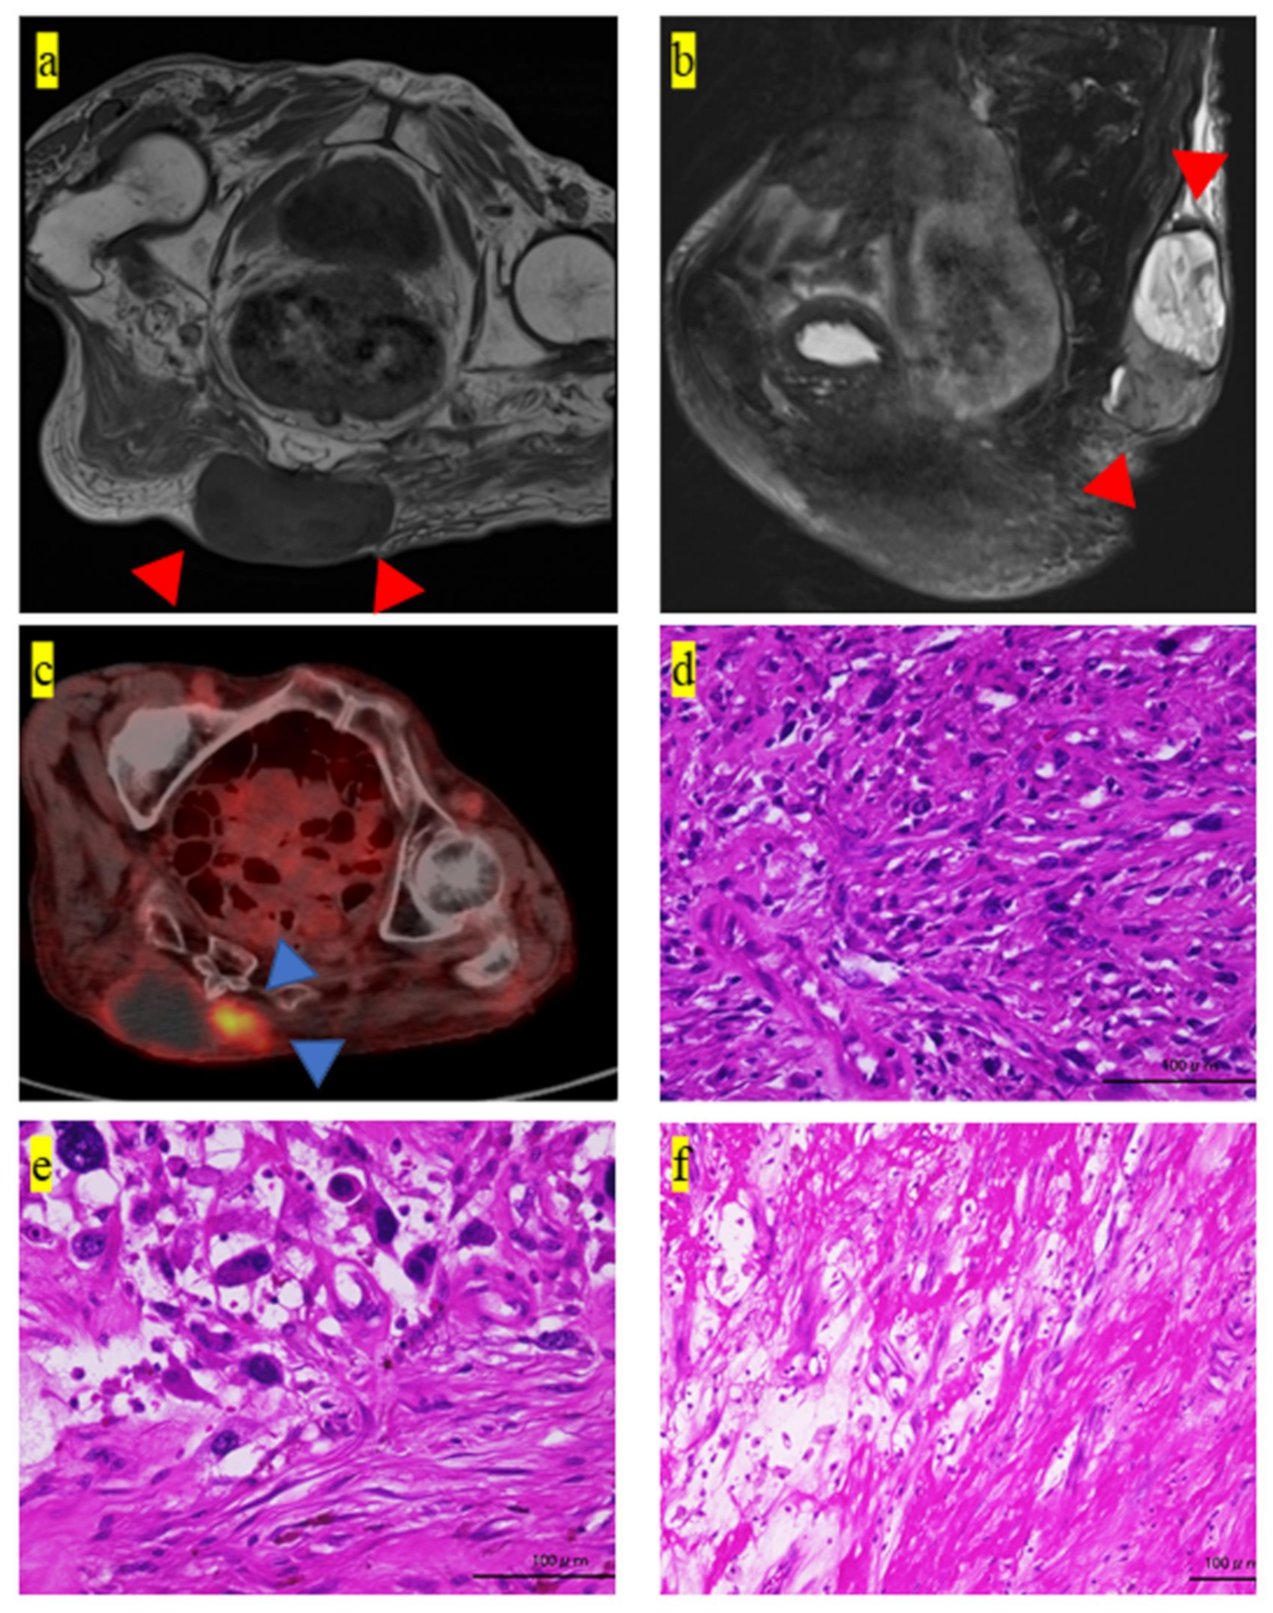

2. Case Presentation